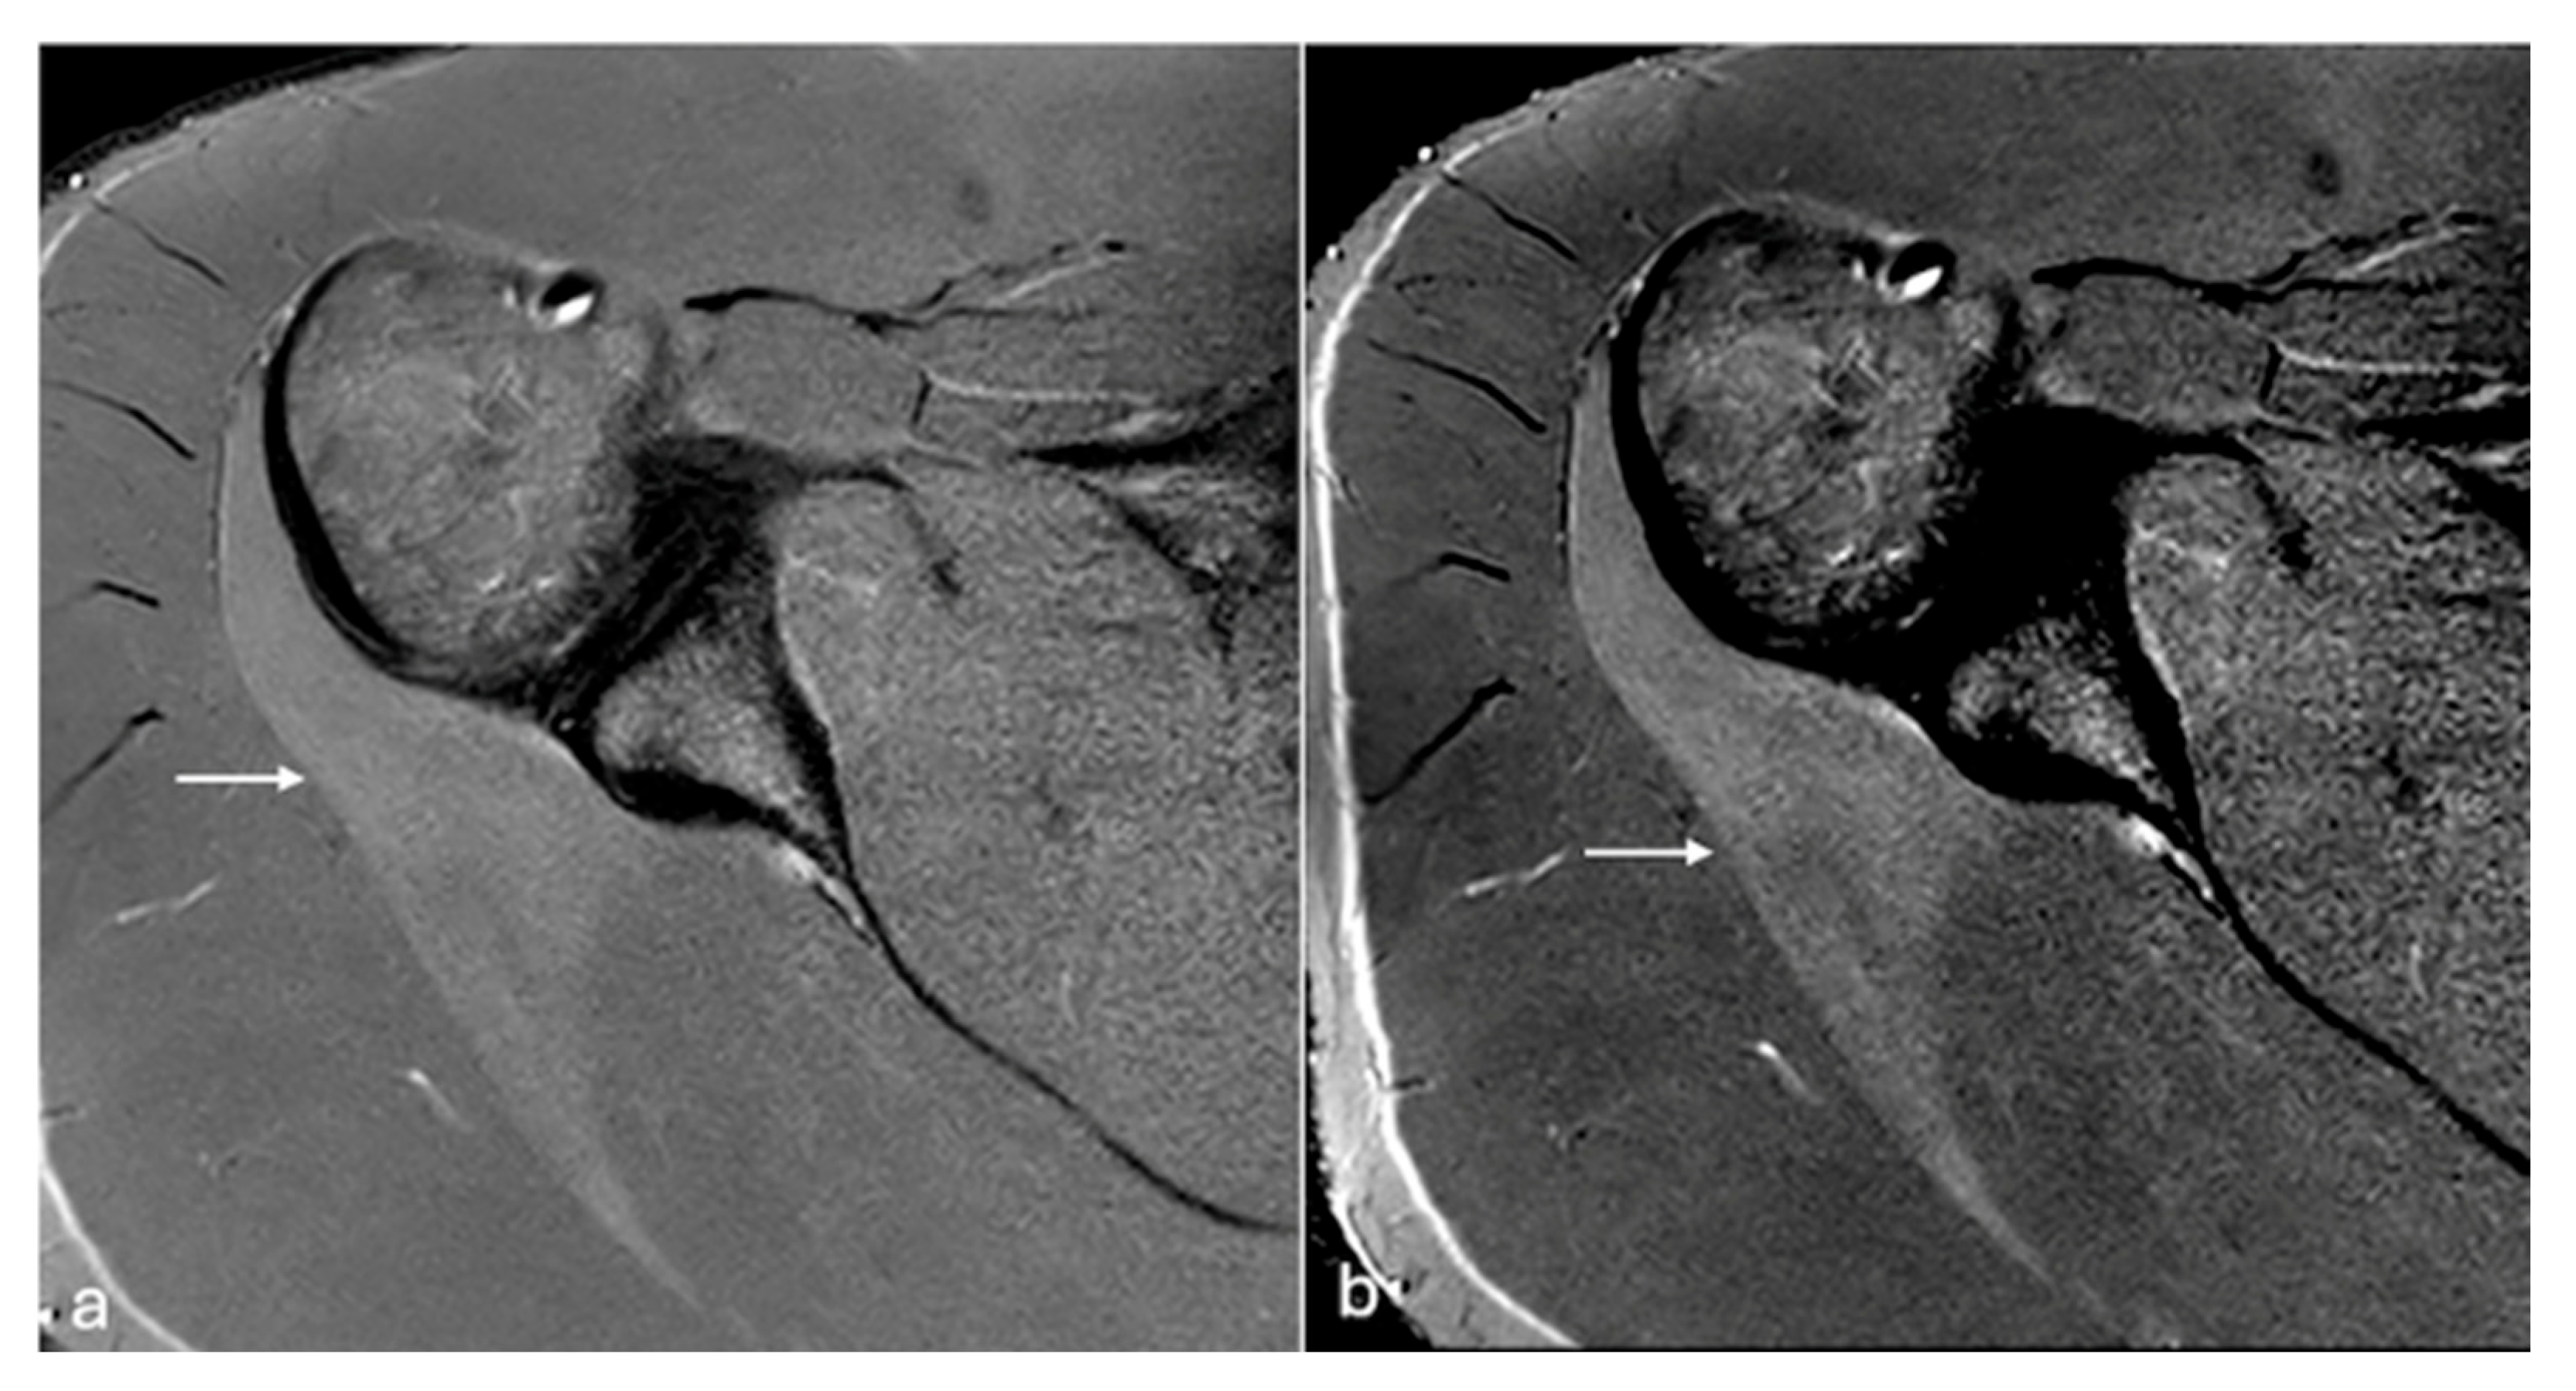

Figure 5. PDFS axial MR images of the left thigh (a,b). Soft tissue oedema changes seen in vastus medialis (arrow) are better delineated on default window image (a) in comparison to modified windowing (b). W/L of the image (a)—1804/851, (b)—902/930.